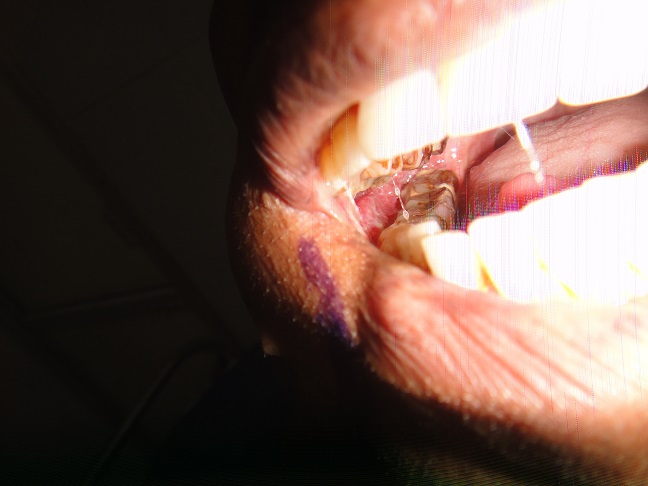

32 YEARS OLD MALE SUFFERING FROM RIGHT LOWER GINGIVO BUCCAL MUCOSA CARCINOMA INVOLVING RIGHT RETROMOLAR TRIGONE.PATIENT HAS ACTIVE PULMONARY TUBERCULOSIS.RIGHT RADICAL NECK DISSECTION WITH RIGHT DISTAL MANDIBULECTOMY WITH RIGHT LOWER ALVEOLECTOMY WITH RIGHT PECTORALIS MAJOR MYOCUTANEOUS FLAPE DONE.

31-12-2021